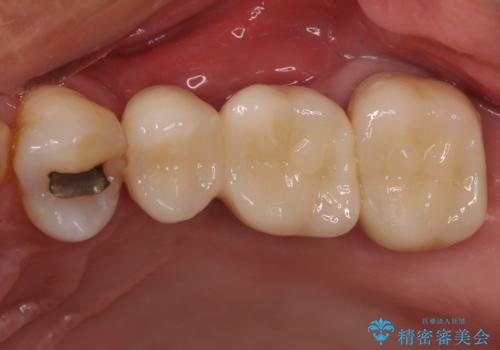

部分矯正を併用した奥歯のインプラント補綴治療

- 奥歯を他院で抜歯した後、インプラント治療を希望とのことで来院された患者様です。

ブリッジの支台を抜歯したことで2本のインプラントが必要であり、その後方はインプラント埋入に必要な骨量が不足していたため、上顎洞粘膜の挙上を行うこととしました。

また、残っている最後方歯は手前に倒れてきていたため、部分矯正により奥に移動させてから、インプラント埋入を行うこととしました。

部分矯正期間中はアンカースクリューやフック、ゴムなどが粘膜にあたり、大変な思いをすることになりましたが、そのおかげでインプラント補綴した歯と最後方歯の位置が非常に良好となり、まるでご自身の歯のように咬むことができるようになりました。